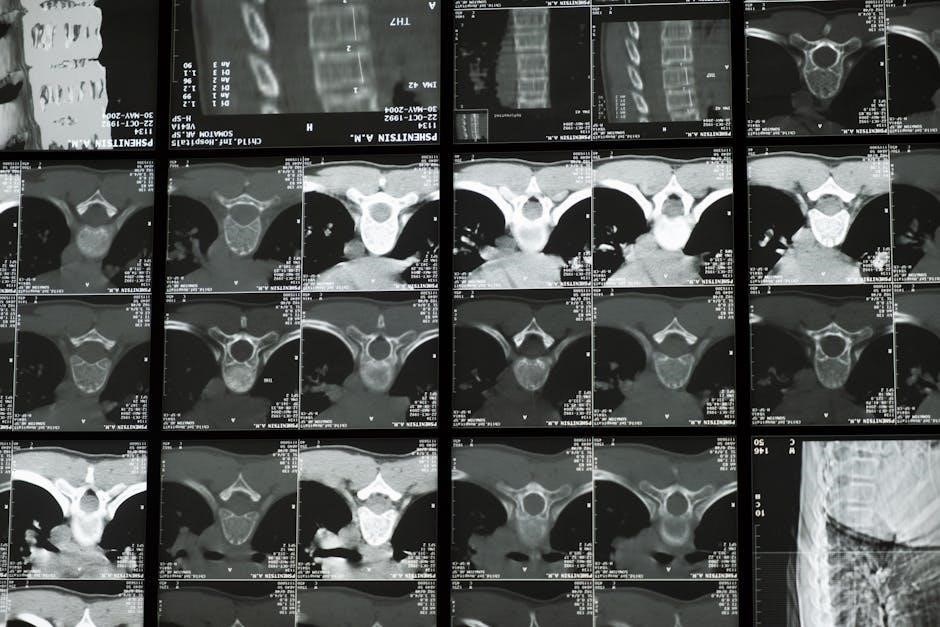

The thoracic spine, comprising twelve vertebrae, connects the cervical and lumbar regions; This mid-back section articulates with the ribs, influencing breathing and posture. This PDF emphasizes understanding its role as a crucial link between the upper and lower body, impacting shoulder and neck function significantly.

Anatomy of the Thoracic Spine

The thoracic spine features twelve vertebrae (T1-T12), each with facets for rib articulation. These ribs contribute to the rib cage, protecting vital organs. Costovertebral joints connect ribs to vertebrae, influencing rotation. Understanding this anatomy, detailed in the PDF, is key to targeted mobility exercises.

The thoracic spine, comprising twelve vertebrae, connects the neck and lower back. It articulates with the ribs, creating a crucial link between the axial skeleton and limbs. This PDF emphasizes understanding its unique structure and function, as hypomobility impacts scapular movement and overall posture, necessitating targeted mobility work.

The thoracic spine features twelve vertebrae (T1-T12), each with costal facets for rib articulation. These ribs, along with associated muscles, limit excessive motion but enable rotation. Understanding this anatomy, detailed in the PDF, is key to performing exercises safely and effectively, restoring optimal spinal mechanics.